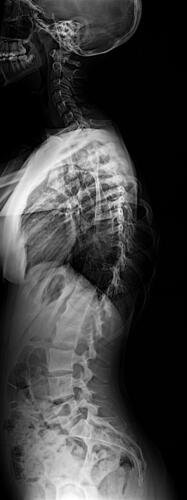

A Vá tem 13 anos e precisa urgentemente realizar uma cirurgia na coluna.Valentina foi surpreendida com o diagnóstico de escoliose hepática grave com 67 graus de desvio (desvio longitudinal da coluna), e precisa realizar com urgência a cirurgia corretiva, os exames foram realizados em Porto Alegre, mas a cirurgia está marcada para dia 13/07 em São Paulo devido a gravidade do caso, para isso a família terá que ficar residindo próximo ao hospital em São Paulo por no mínimo 30 dias para uma plena recuperação. Sabemos bem que qualquer procedimento cirúrgico é delicado, na coluna então nem se fala.Após o diagnóstico e o prognostico dessa doença a família se desfez de alguns bens (carro e moto) para cumprir os prazos dos exames e consultas, necessitando agora arrecadar o valor para a estadia da pequena Valentina e seu pós operatório (medicação, consultas e fisioterapia).

Em anexo os exames (laudo e imagens) para expressas a gravidade do caso.